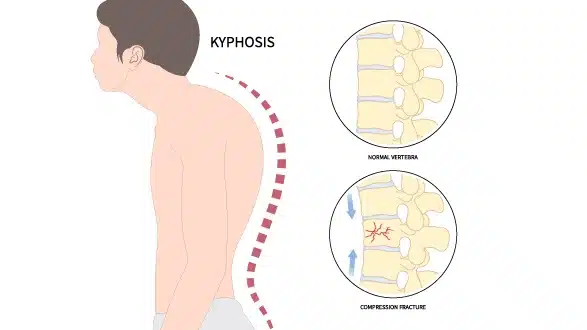

Kyphosis

A condition characterised by an abnormal forward curvature of the spine

Kyphosis is a spinal condition characterised by an exaggerated forward curve of the upper back, sometimes described as a rounded or hunched posture. While some curvature in the thoracic spine is normal, excessive curvature may cause back pain, stiffness, reduced mobility, or visible changes in posture.

Kyphosis can occur at any age. In younger people it may result from conditions such as Scheuermann’s disease or congenital spinal differences, while in older adults it is more often linked to degenerative changes, osteoporosis, or vertebral fractures.

The impact of kyphosis varies. Some cases cause minimal symptoms, while more severe curvature can affect breathing, balance, or overall function. Management depends on the underlying cause, the degree of curvature, and the severity of symptoms, and may include physiotherapy, bracing, or surgery in selected cases.

- Osteoporosis – Weakening of the bones in older adults can cause compression fractures in the vertebrae, resulting in increased curvature.